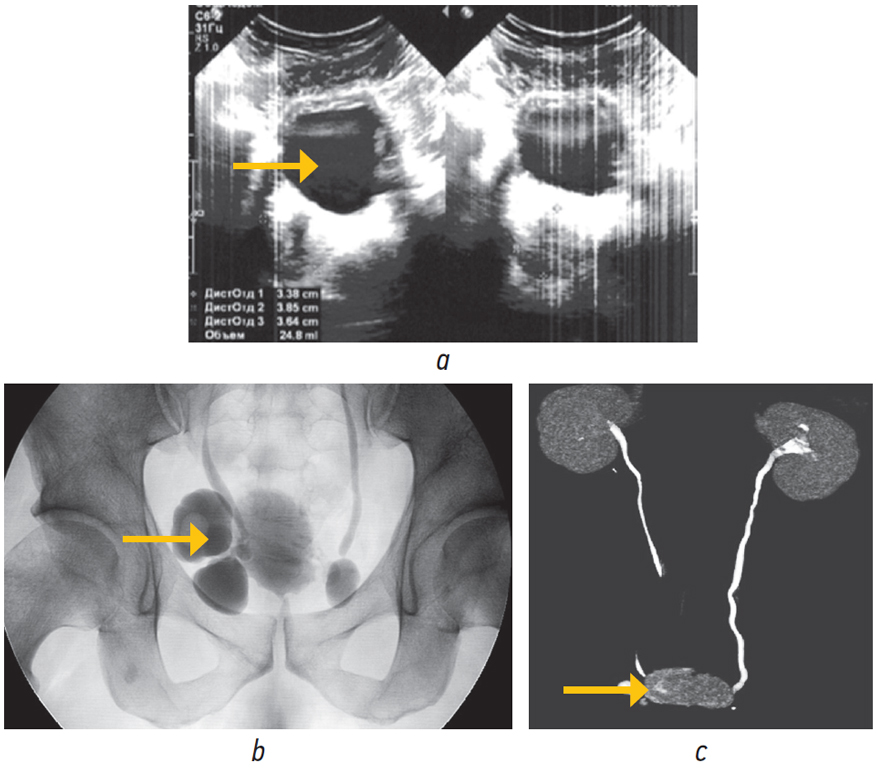

Пациент Т., 37 лет, обратился за медицинской помощью с жалобами на учащенное мочеиспускание, ослабление струи мочи. Из анамнеза известно, что при прохождении планового обследования в общем анализе мочи выявлена лейкоцит- и эритроцитурия. Пациенту проведен дополнительный стандарт лабораторных исследований. Заполнен опросник IPSS, по данным которого пациент набрал 4 балла, что расценивалось как легкая симптоматика, по шкале QoL — 2 балла. Несмотря на удовлетворительную субъективную оценку мочеиспускания, показатели уро флоуметрии были ниже пороговых значений: максимальная скорость мочеиспускания — 7,1 мл/с, средняя — 3,8 мл/с. По данным ультразвукового исследования выявлены множественные (3) дивертикулы мочевого пузыря, размерами 40 мм, 21 мм и 15 мм, объем предстательной железы 25 см3, объем остаточной мочи 150 мл, также в одном из дивертикулов выявлен камень. После выполнения внутривенной урографии и компьютерной томографии наличие множественных дивертикулов мочевого пузыря и камня одного из них было подтверждено (рис. 2).

Рис. 2. Результаты обследования больного Т., 37 лет: a — ультразвуковая картина мочевого пузыря с дивертикулами; b — нисходящая цистография, камень в дивертикуле мочевого пузыря; с — компьютерная томография-урография с 3D-реконструкцией, камень дивертикула правой боковой стенки мочевого пузыря (указан стрелкой) / Fig. 2. The results of the examination of the patient T., 37 years old: a — ultrasound picture of the bladder with bladder diverticula; b — descending cystography, bladder diverticulum stone; c — computed tomography-urography with 3D reconstruction, stone in the diverticulum of the right lateral wall of the bladder (indicated by an arrow)